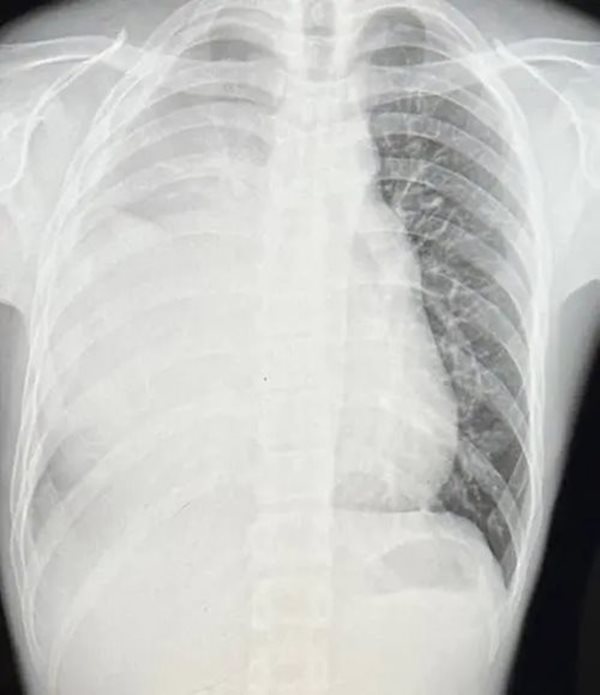

หนุ่มวัย 21 ปี ชอบเล่นกีฬา ไม่สูบบุหรี่ กลับเอกซเรย์เจอปอดขาวโพลน แพทย์ชี้ จะเหลือปอดข้างเดียวตลอดชีวิต

วันที่ 4 พฤศจิกายน 2566 เว็บไซต์ ETtoday เผยเรื่องราวชวนสะเทือนใจของชายหนุ่มรายหนึ่งในไต้หวัน เมื่อเร็ว ๆ นี้เขาได้ออกมาแชร์เรื่องราวผ่านทาง Dcard ชุมชนออนไลน์จนกลายเป็นประเด็นที่ได้รับความสนใจ โดยเขาเผยว่า เขาเป็นคนไม่สูบบุหรี่ และชอบเล่นกีฬา เป็นวัยรุ่นที่สุขภาพร่างกายแข็งแรงมาก แต่อยู่ ๆ วันหนึ่งกลับพบว่า ปอดของเขากลายเป็นสีขาวไปหมด และต้องเผชิญความจริงที่ว่า เขาจะเหลือปอดเพียงข้างเดียวไปตลอดชีวิต ในขณะที่เขาอายุแค่ 21 ปีเท่านั้น

นอกจากนี้ หลังจากให้เคมีบำบัดครบ 3 รอบ เนื้องอกก็ยังอยู่เหมือนเดิม ไม่ใหญ่ขึ้นหรือเล็กลง แต่กลายเป็นพังผืดที่กำลังจะเป็นเนื้อตาย สิ่งที่ทำให้เขายิ่งทุกข์ใจมากขึ้นคือ หมอบอกว่า เขาจะเหลือปอดแค่ข้างเดียวตลอดชีวิต เขารู้สึกตัวชาไปทั้งตัว แล้วร้องไห้ออกมาทันที คิดกับตัวเองว่า "อายุเราแค่ 21 ปีเท่านั้นเอง"